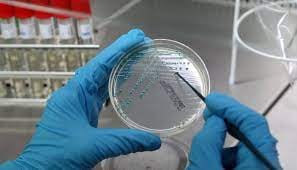

გონორეა ვენერიული დაავადებაა, რომელიც გადაეცემა ძირითადად სქესობრივი გზით. დაავადების გადაცემის არასქესობრივი გზა საკმაოდ იშვიათად გვხვდება, რაც ძირითადად ბავშვებში ვითარდება. იგი ძირითადად აზიანებს შარდ-სასქესო სისტემას, საშვილოსნოს მილებს. მწვავე სტადიაში ავადმყოფები უჩივიან ტკივილს, ჩხვლეტისა და ჭრის შეგრძნებას შარდვის დროს; ქრონიკულ სტადიაში ჩივილები არ აღინიშნება. ანამნეზის საფუძველზე შეგვიძლია დავადგინოთ: დაავადების გამოვლინება სქესობრივი ცხოვრების დაწყებიდან მოკლე პერიოდში, შემთხვევითი სქესობრივი კავშირები. ქალებში, რომელთაც აღენიშნებათ პირველადი უნაყოფობა. მკურნალობის დაწყებამდე ტარდება ბაქტერიოლოგიური და ბაქტერიოსკოპული დიაგნოსტიკა. ნაცხების ციტობაქტერიოლოგიური გამოკვლევისას განასხვავებენ შემდეგ ჯგუფებს: K1 – ნაცხში ლეიკოციტების დიდი რაოდენობაა, ფლორა არ არის, ვლინდება უჯრედშიგა და უჯრედგარე გონოკოკი; K2 – ნაცხში ლეიკოციტების დიდი რაოდენობაა, ფლორა არ არის, გონოკოკები არ ვლინდება; K3 – აღინიშნება ლეიკოციტების უმნიშვნელო რაოდენობა და მრავალფეროვანი მიკრობული ფლორა.